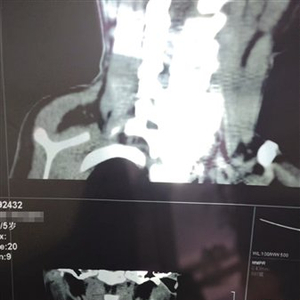

4月7日,星元医院CT结果显示,软管目前位于小白颈部左侧腮腺内。 本版图片/受访者供图

不做手术任由软管继续留在体内也有风险。2024年4月7日,星元医院CT结果显示,软管目前位于小白颈部左侧腮腺内。白海海告诉新京报记者,小白今年已经在上幼儿园大班,软管留置体内的5年多,“娃娃没说过身体不舒服,也没有特别的感觉”,但西安市儿童医院出院记录上的一行字像根刺一样扎在他心上——“考虑(异物)已在血管内漂移,可能至心、肺部”,他担心,这截随着血液游动的软管早晚有一天会像炸弹一样引爆,影响小白的健康,甚至危及生命。